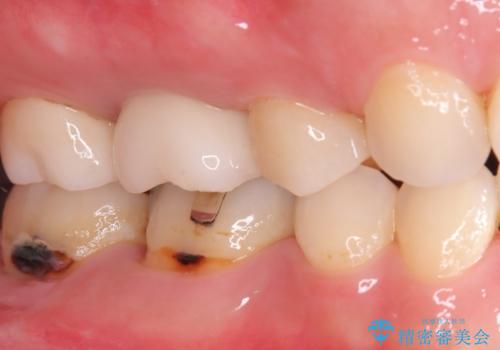

- 右下6番と7番の奥歯に、歯の根元部分の虫歯(根面カリエス)を認め来院されました。通常の虫歯よりも進行しやすい根面カリエスは、再発リスクを抑えた治療が重要です。患者様のご希望と口腔内の状態を考慮し、虫歯を徹底的に除去し、精密で耐久性の高いセラミッククラウンで修復する治療計画を立案しました。これにより、長期的な再発防止と咬み合わせの機能回復を目指します。

治療ではまず、感染した歯質をマイクロスコープで確認しながら慎重に除去。その後、セラミッククラウンを装着するための歯の形成を行いました。型取りから患者様の歯の形や色に合わせたオーダーメイドのセラミッククラウンを作製。セラミックは、プラークが付着しにくく、再治療のリスクを低減する特性があります。最終的に、精度の高いクラウンを装着し、咬み合わせを細かく調整しました。これにより、根面カリエスが再発しにくい環境を整え、快適に食事ができる奥歯を取り戻していただけました。